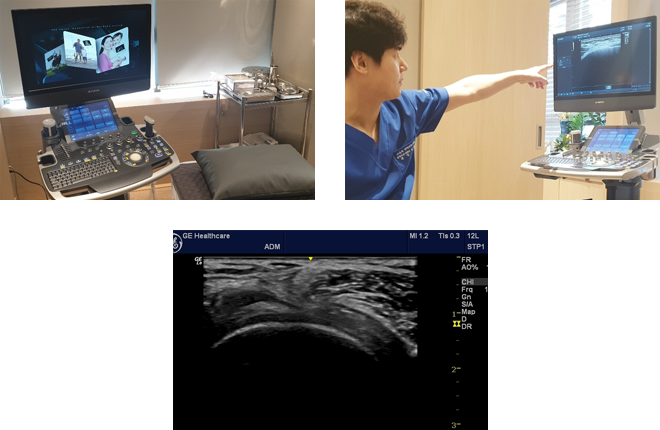

대치역삼바른길정형외과의원에서는 안전하고 정확한 시술을 위해

정확도가 뛰어난 정밀진단 장비를 사용하고 있습니다.

인체에 무해한 초음파를 이용하여 신경과 혈관을

피해 정밀한 주사치료가 가능합니다.